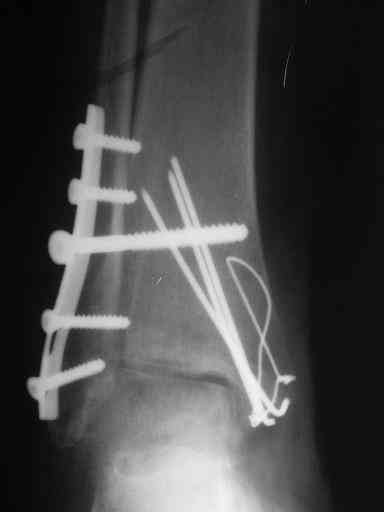

ANDREW 14 Май 2010, 23:44

Завершая презентацию случая хотим показать результат операции. Прооперировали больную в соседнем отделении. На операции выраженый рубцовый процес в области синдесмоза, остеопоротические изменения в области медиальной и латеральной лодыжек. Провели удаление рубцовой ткани, остеосинтез медиальной и латеральной лодыжек с позиционным винтом на синдесмоз. Фото прилагаем. Благодарим за отзывы.